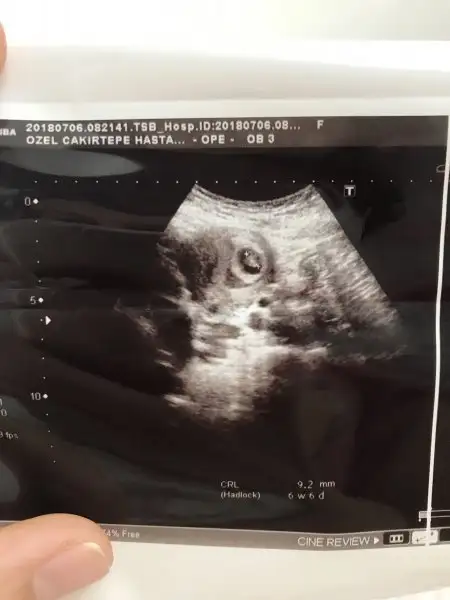

doktora gittim geldim. bebeği ve kalp atışlarını gördüm . 160 atıyor dedi. herşey yolunda 6+5 deyim.